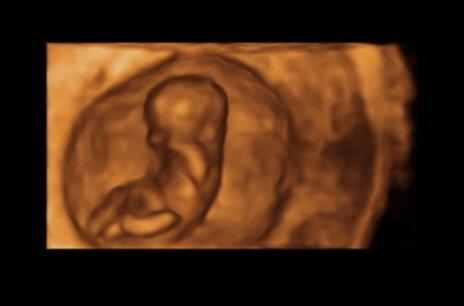

Hallihallo, nach langen 4 Wochen hatte ich heute nun wieder VU. Es ist alles in bester Ordnung, das Würmchen hat sich von seiner besten Seite gezeigt und ist jetzt 3,5 cm klein. Liebe, glückliche Grüße.

Bild zu Heute VU - mit Bildchen - Forum für März - Mamis

oh cool 3 D oder 4 d :D :D

4 D